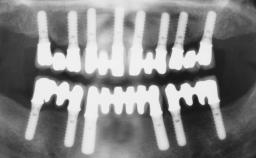

Conventional Loading of Eight Implants in the Maxilla and Final Restoration with a Full-Arch Gold-Ceramic FDP

A 35-year-old Caucasian female presenting with advanced periodontal disease involving both the maxillary and the mandibular dentition was referred for evaluation. The patient, a non-smoker in good general health, requested treatment for recurrent periodontal abscesses, tooth mobility, and discomfort during chewing, as well as restoration of her missing teeth with a fixed prosthesis to improve mastication and esthetics. All residual maxillary teeth exhibited plaque deposits, deep pockets, bleeding on probing, and class III mobility and were evaluated as hopeless. All residual mandibular teeth except tooth 37 could be maintained after periodontal therapy.